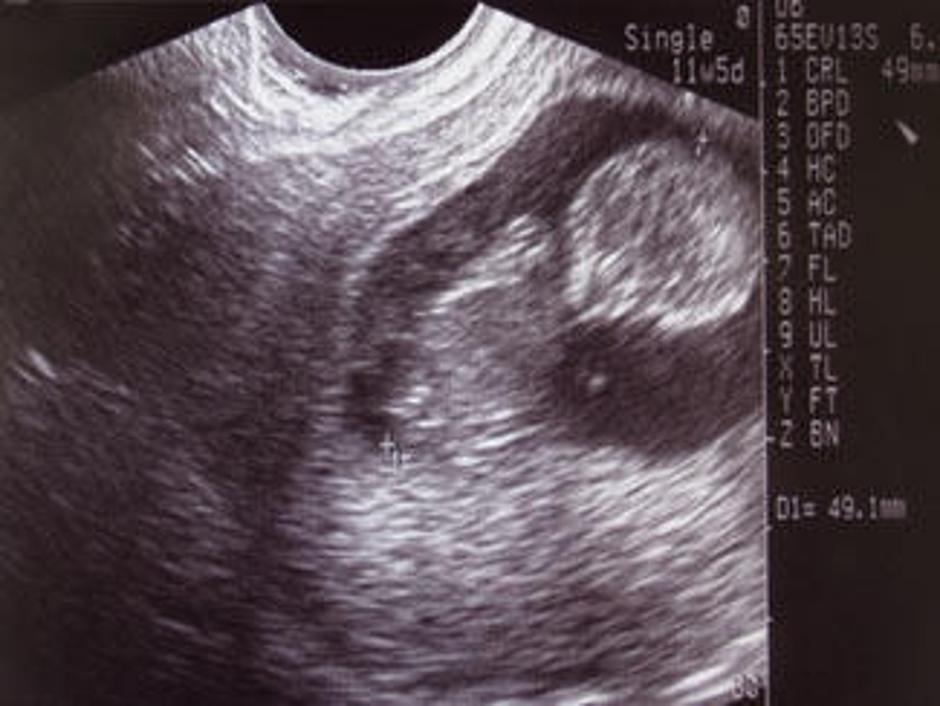

ultrazvok plod Slovenija Uzakonili pravico do pokopa splavljenih otrok

(Foto: istockphoto) Starša ne smeta pokopati mrtvorojenke Slovenija Starša ne smeta pokopati mrtvorojenke